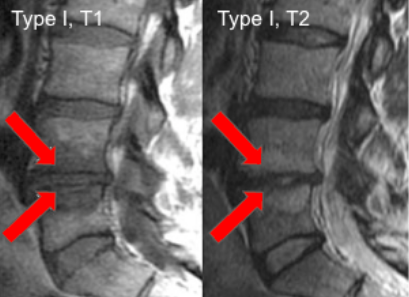

Image Type Lumbar Spine X-Ray CT Scan MRI Scan Anteroposterior (AP) Canal Diameter Cauda Equina Nerve Root Area Conus Medullaris Level Cross-Sectional Area (CSA) of Spinal Canal Disc-Height Index (DHI) Disc Herniation Size Disc Herniation Types Dural Sac CSA Epidural Fat Thickness Filum Terminale Thickness Foraminal Height and Width High-intensity Zone (HIZ) Lateral Recess Width/Depth Modic Endplate Changes (Type I, II, III) Modic (Marrow Signal) Changes Pfirrmann Classification (I-V) Vertebral Bone Quality (VBQ) Score Vertebral Endplate Defects